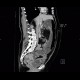

The most prominent finding in this examination was massive dilation of the colon with air-fluid levels indicating bowel obstruction (ileus). Its cause can be tracked down to sigmoid, where a tumorous thickening of the wall with extension into the mesosigmoid and involvement of local lymph nodes can be found. Small bowel loops remain relatively undistended thanks to competence of the ileocecal valve.